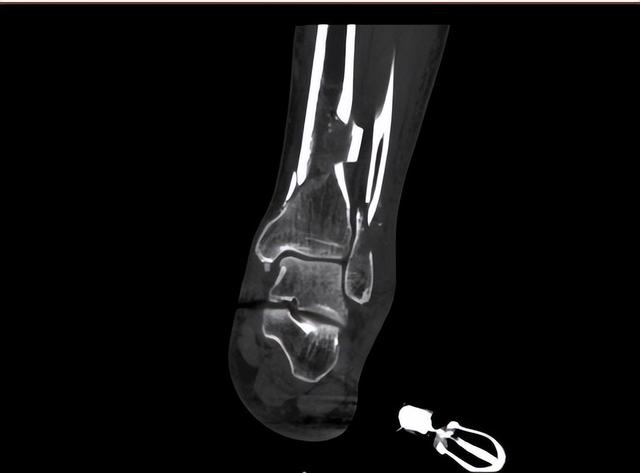

行车安全要注意:一位39岁男性患者车祸,致左小腿粉碎性骨折-2.jpg

患者共住院治疗23天,出院时术口恢复可,已拆线,支具佩戴中,拄拐行走,肢端血供可,左踝活动可,感觉无明显异常,复查左胫腓骨X片,提示骨折对位对线可,内固定装置正常。患者要求出院,遂予以出院,嘱其日常活动不要用患肢负重,一月后专家门诊复查。后续数次复诊,患者逐渐痊愈。

行车安全要注意:一位39岁男性患者车祸,致左小腿粉碎性骨折-3.jpg